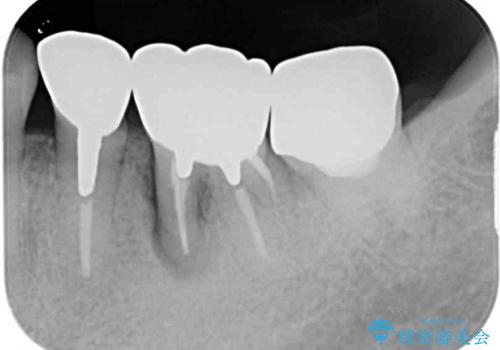

診断の結果、奥歯は歯根が破折しており、抜歯が必要な状況でした。

インプラントあるいはブリッジによる補綴治療が考えられましたが、前後の歯が大きな銀歯であったため、オールセラミックブリッジにより3本の歯を審美的に仕上げることとしました。

ブリッジの支台歯は2本とも神経を取り除いている歯であるため、咬合力の強い方ですと、支台歯も歯根破折をするリスクがあります。

今回はそれほど咬合力が強いとは思われなかったため、ブリッジによる補綴治療を行いましたが、念のため、就寝時にはナイトガードとしてマウスピースを装着するようお願いしました。